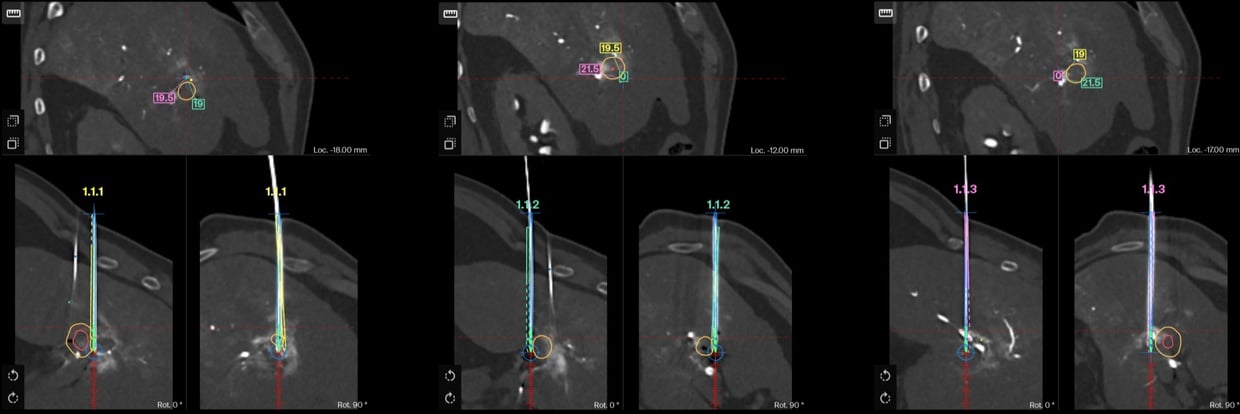

IRE of an HCC recurrence in segment V under intra-arterial CT guidance

A 69 years old patient diagnosed with an HCC and treated previously by a left lobectomy in 2020, underwent combined TACE and IRE after a first recurrence near the hepatic hilum. Two years later, a local recurrence at the same site was retreated with IRE under angio-CT guidance (intra-arterial contrast) using the CAS-One IR system. AblaSure confirmed complete tumor coverage and 98% margin attainment. The procedure was rapid, uneventful, and efficient.

Planning scan showing the lesion and the SmartMargin tool defining the target margins while excluding the hepatic artery.

- The lesion near the hepatic hilum was accurately segmented after intra-arterial contrast injection using the SmartMargin tool.